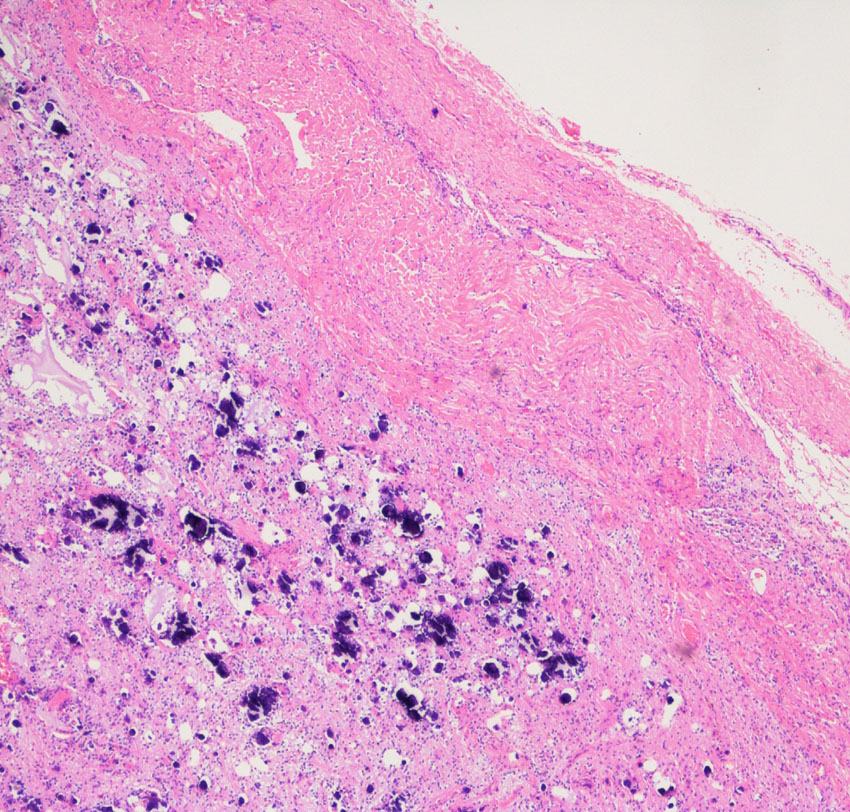

厚く肥厚した視神経鞘の内部の視神経組織はほとんど腫瘍に置き換わっていて,GFAPで染色され高度の石灰化を伴います。これは腫瘍というよりも瘢痕化してしまった,adult-type pilocytic astrocytomaに認められる所見です。

Rosenthal fiber, eosinophyric granular body, psammoma bodyなどが認められ,成熟しきって退行変性に移行するpilocytic astrocytomaの像です。この部分は増大しません。線維性に極めて硬い組織です。